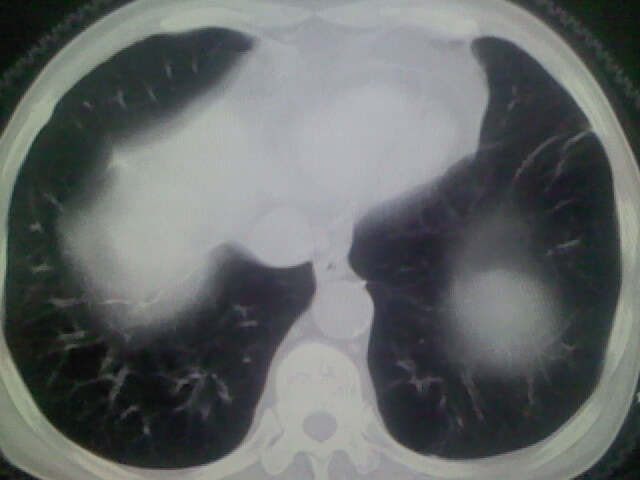

男,70y,胃占位,重度贫血,黑便3月余,伴恶心,纳差,乏力

肺内考虑原发(周围型肺癌)

右上肺周围型肺癌,肝内多发低密度影---转移瘤?建议增强;胃壁明显增厚.

右上肺周围型肺癌,肝内多发低密度影---转移瘤.

1)考虑右肺上叶周围型肺癌并纵隔及右颈部淋巴结转移,肝脏多发性转移。2)肺气肿。3)冠状动脉及主动脉钙化。